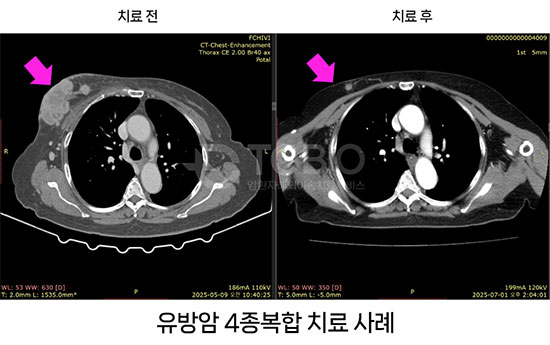

4종 복합치료를 통해 설암 4기 환자와 간암환자, 간문부담관암(Klatskin's tumor), 유방암(삼중음성 유방암 포함)에 대해서 완전 관해 사례가 나왔다고 한다. 이 외에도 위암, 난소암, 대장암, 신장암, 방광암, 전립선암. 등등 우수한 치료결과 사례들이 지속적으로 나오고 있어 더욱 주목을 받고 있다고 한다.

이 복합치료는 표준치료에서 어려운 복막 전이, 뼈 전이에서도 치료가 가능하고, 부작용이 거의 없을 뿐만 아니라 치료 기간도 짧고 결과 확인도 4주째 확인할 수 있다는 가장 큰 장점이 있다. 심지어는 당장 중입자치료가 불가능 한 경우도 이런 복합치료로 호전시킨 후, 중입자치료 양성자치료를 시행하여 완치한 경우도 있어서, 표준치료만 고집해서 몸상태를 악화시키기 보다는 이런 치료방법을 고려해 보는 것도 바람직하다.